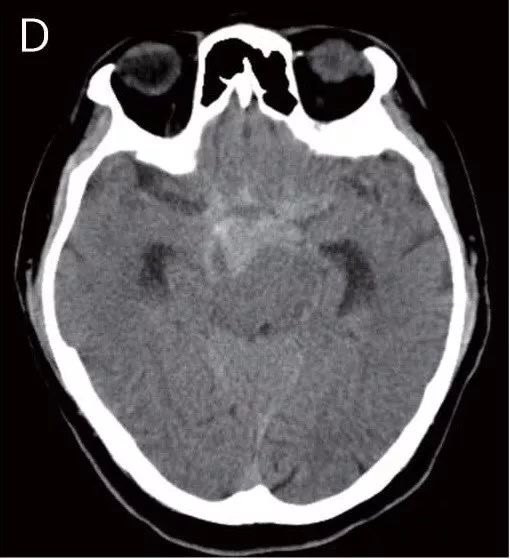

teaching neuroimages: vertebrobasilar dolichoectasia with

图片尺寸510x559